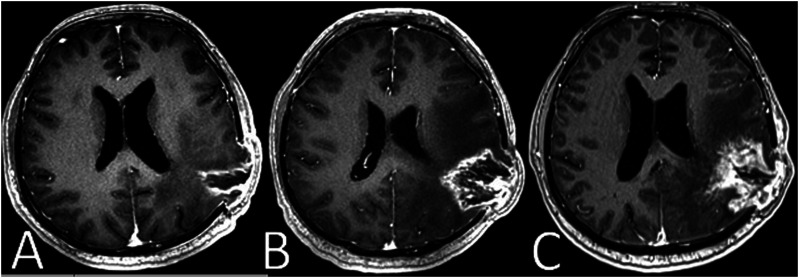

Case reports: Case 1 discusses a 41-year-old male with GBM, highlighting the challenges of differentiating tumor progression from treatment-induced pseudoprogression. Case 2 discusses a 45-year-old female with brain metastatic malignant melanoma, presenting radiological evidence of progressive disease while undergoing nivolumab treatment. Case 3 discusses a 37-year-old male with GBM, where radiological evidence indicates progressive disease while receiving pembrolizumab treatment.

Management and outcomes: In case 1, we discussed the challenges of distinguishing true tumor progression from treatment-induced pseudoprogression, leading to the continuation of the same treatment due to pseudoprogression. In case 2, post-surgery pathology revealed radionecrosis and treatment-related changes, guiding the continuation of nivolumab therapy. Case 3 involved a pathologically confirmed progression, and the patient received best supportive care due to his performance status.